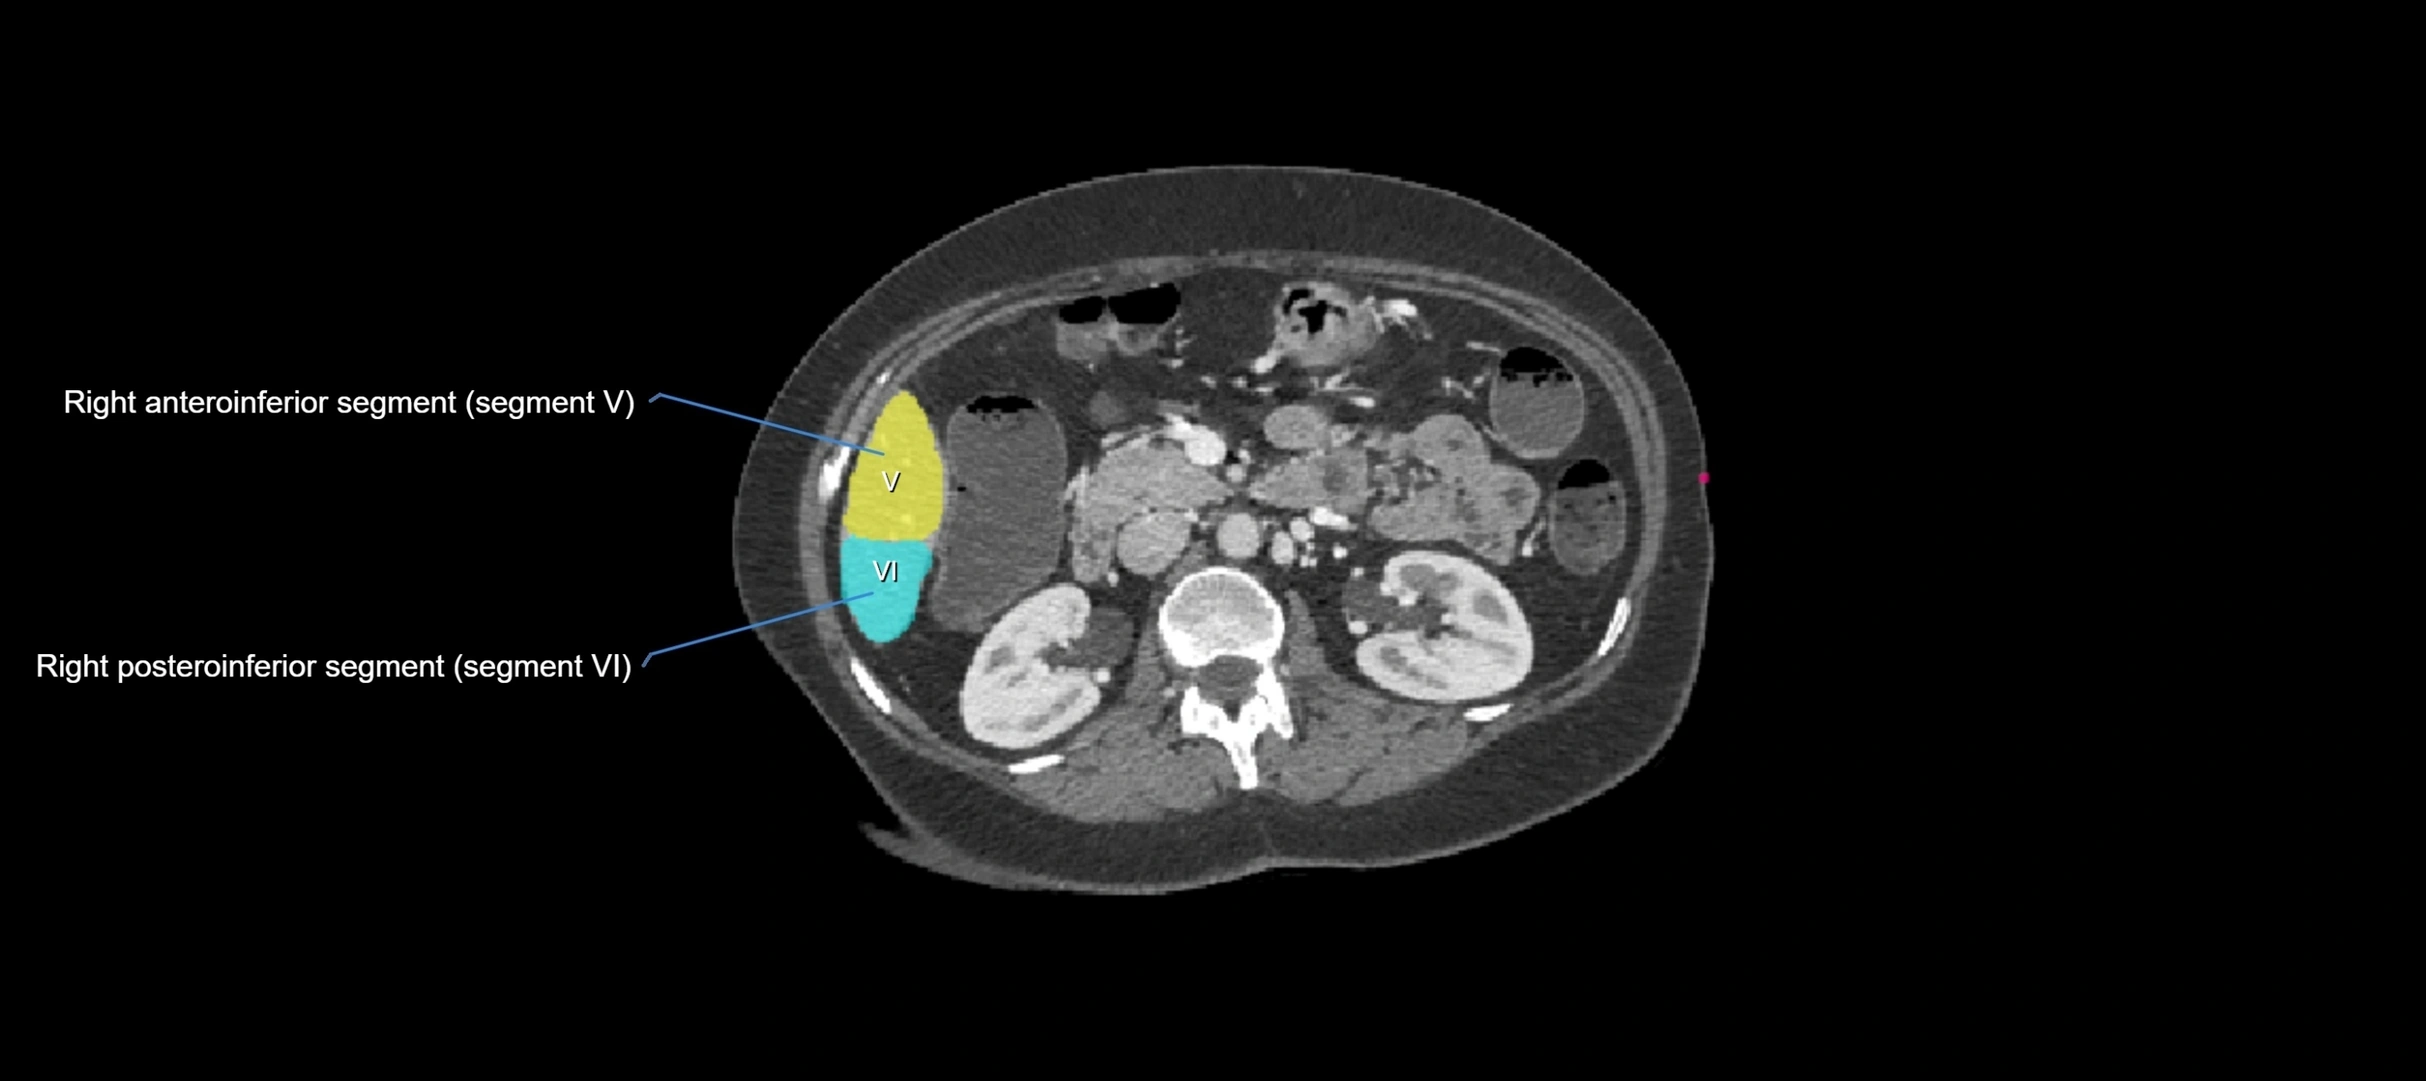

CT Appearance

CT Pre-Contrast:

• Caudate lobe appears as a soft-tissue density, isodense to the rest of the liver

• Enlargement may be appreciated in cirrhosis or Budd–Chiari syndrome

CT Post-Contrast:

• Homogeneous enhancement in the portal venous phase, similar to rest of liver

• Independent venous drainage into the IVC may be visualized

• Lesions follow characteristic CT enhancement patterns (HCC: arterial hyperenhancement with washout; hemangiomas: peripheral nodular enhancement with centripetal fill-in)

CT Venous Phase (functional significance):

• Caudate lobe often enhances relatively more than other lobes in Budd–Chiari syndrome, due to preserved venous outflow